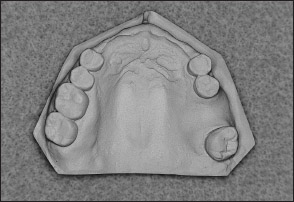

• Kennedy Class III arch: Presents a unilateral edentulous area with natural teeth both anterior and posterior to it (Figs 1-15 and 1-16).

Fig 1-15 Maxillary Kennedy Class III arch.

Fig 1-16 Mandibular Kennedy Class III arch.